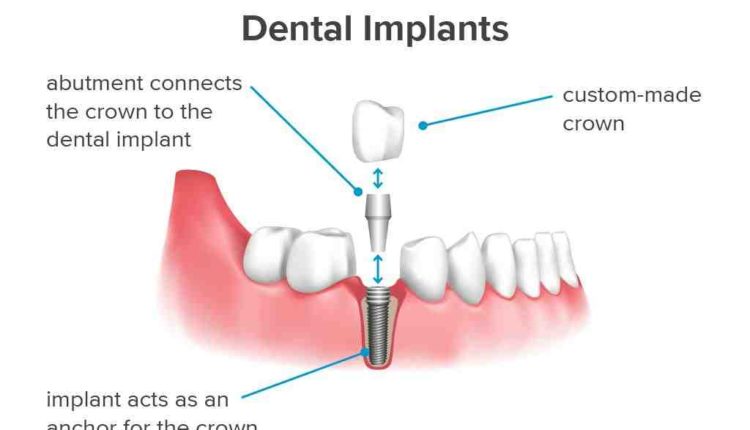

If you have ever wondered why you sell teeth at such a high price, the reasons are: Tooth decay is a cosmetic and difficult task. You pay for the skills of a dentist. The implants and dental crowns add to the cost.

The average cost of installing a full mouthpiece is about $ 34,000. Upper or lower dental implants can cost $ 3,500 to $ 30,000. Full dental equipment is strong and reliable.

How long does it take for dental implants to settle?

How long does it take to install the teeth to settle? It takes an average of six to eight months for implanted teeth to fully heal to the point where you can resume your daily routine without help.

The risks and complications of taking dental implants include infection, damage to other teeth, delayed bone healing, nerve damage, prolonged bleeding, fractures and more. If you are ready to take these risks, dental implants are right for you.